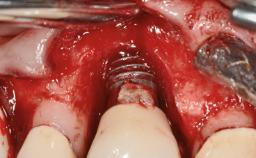

Peri-implantitis Modified by Submucosal Excess of Cement: Regenerative Peri-implantitis Therapy and Six-year Follow-up

A 30-year-old female patient was referred to the Department of Periodontology of the University of Bern, Switzerland, by a dentist in private practice. Tooth 45 had been congenitally missing and had been replaced with a titanium implant three years prior to the first visit at the Department of Periodontology. The tissue level implant had a diameter of 4.1 mm, a length of 12 mm, and a sandblasted and acid-etched (SLA) surface (Straumann® Dental Implant System; Institut Straumann AG, Basel, Switzerland). The metal-ceramic crown on implant 45 had been cemented permanently. Implant 45 had been diagnosed with peri-implantitis by the referring dentist in the course of regular supportive care.